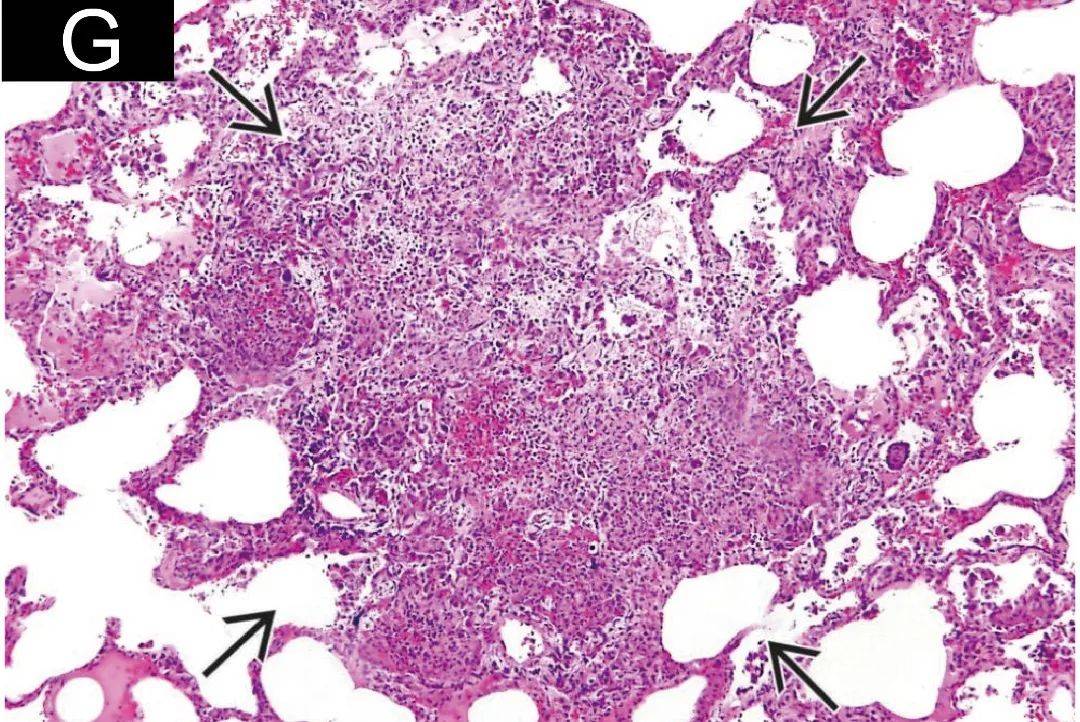

与周围肺实质界限清楚,有炎性细胞浸润;i:弥漫性间质性肺炎cmv感染

特发性间质性肺炎的病理影像特点